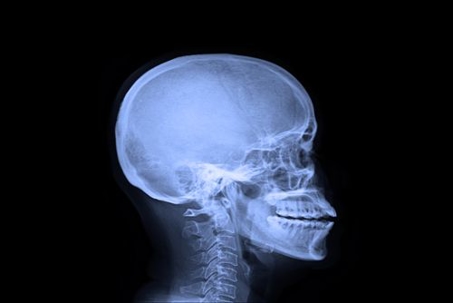

xray of a skull